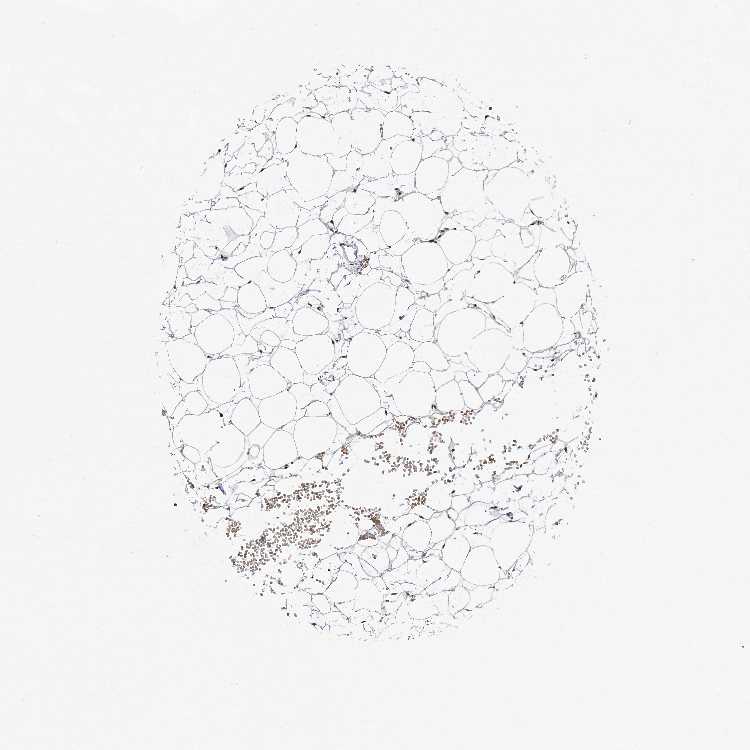

ADIPOSE TISSUE - Antibody stainingi

Antibody staining in the annotated cell types in the current human tissue is reported as not detected, low, medium, or high, based on conventional immunohistochemistry profiling in selected tissues. This score is based on the combination of the staining intensity and fraction of stained cells.

Each image is clickable and will lead to virtual microscopy that enables deeper exploration of all samples and also displays staining intensity scores, fraction scores and subcellular localization as well as patient and tissue information for each sample.

Antibody CAB037214Antibody CAB037285

Adipocytes Not detectedMedium